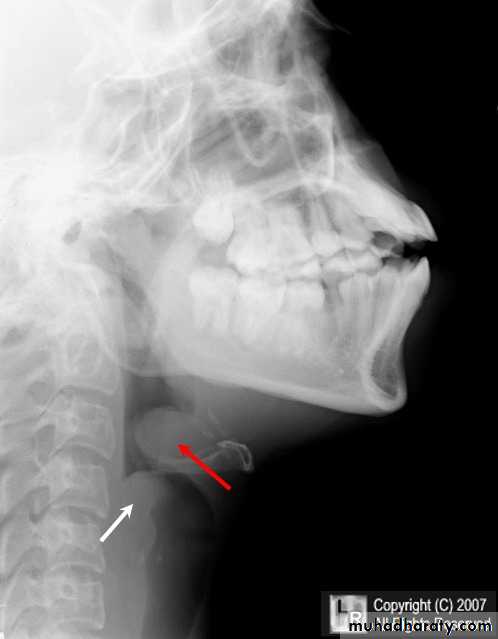

Radiology: thumb print sign